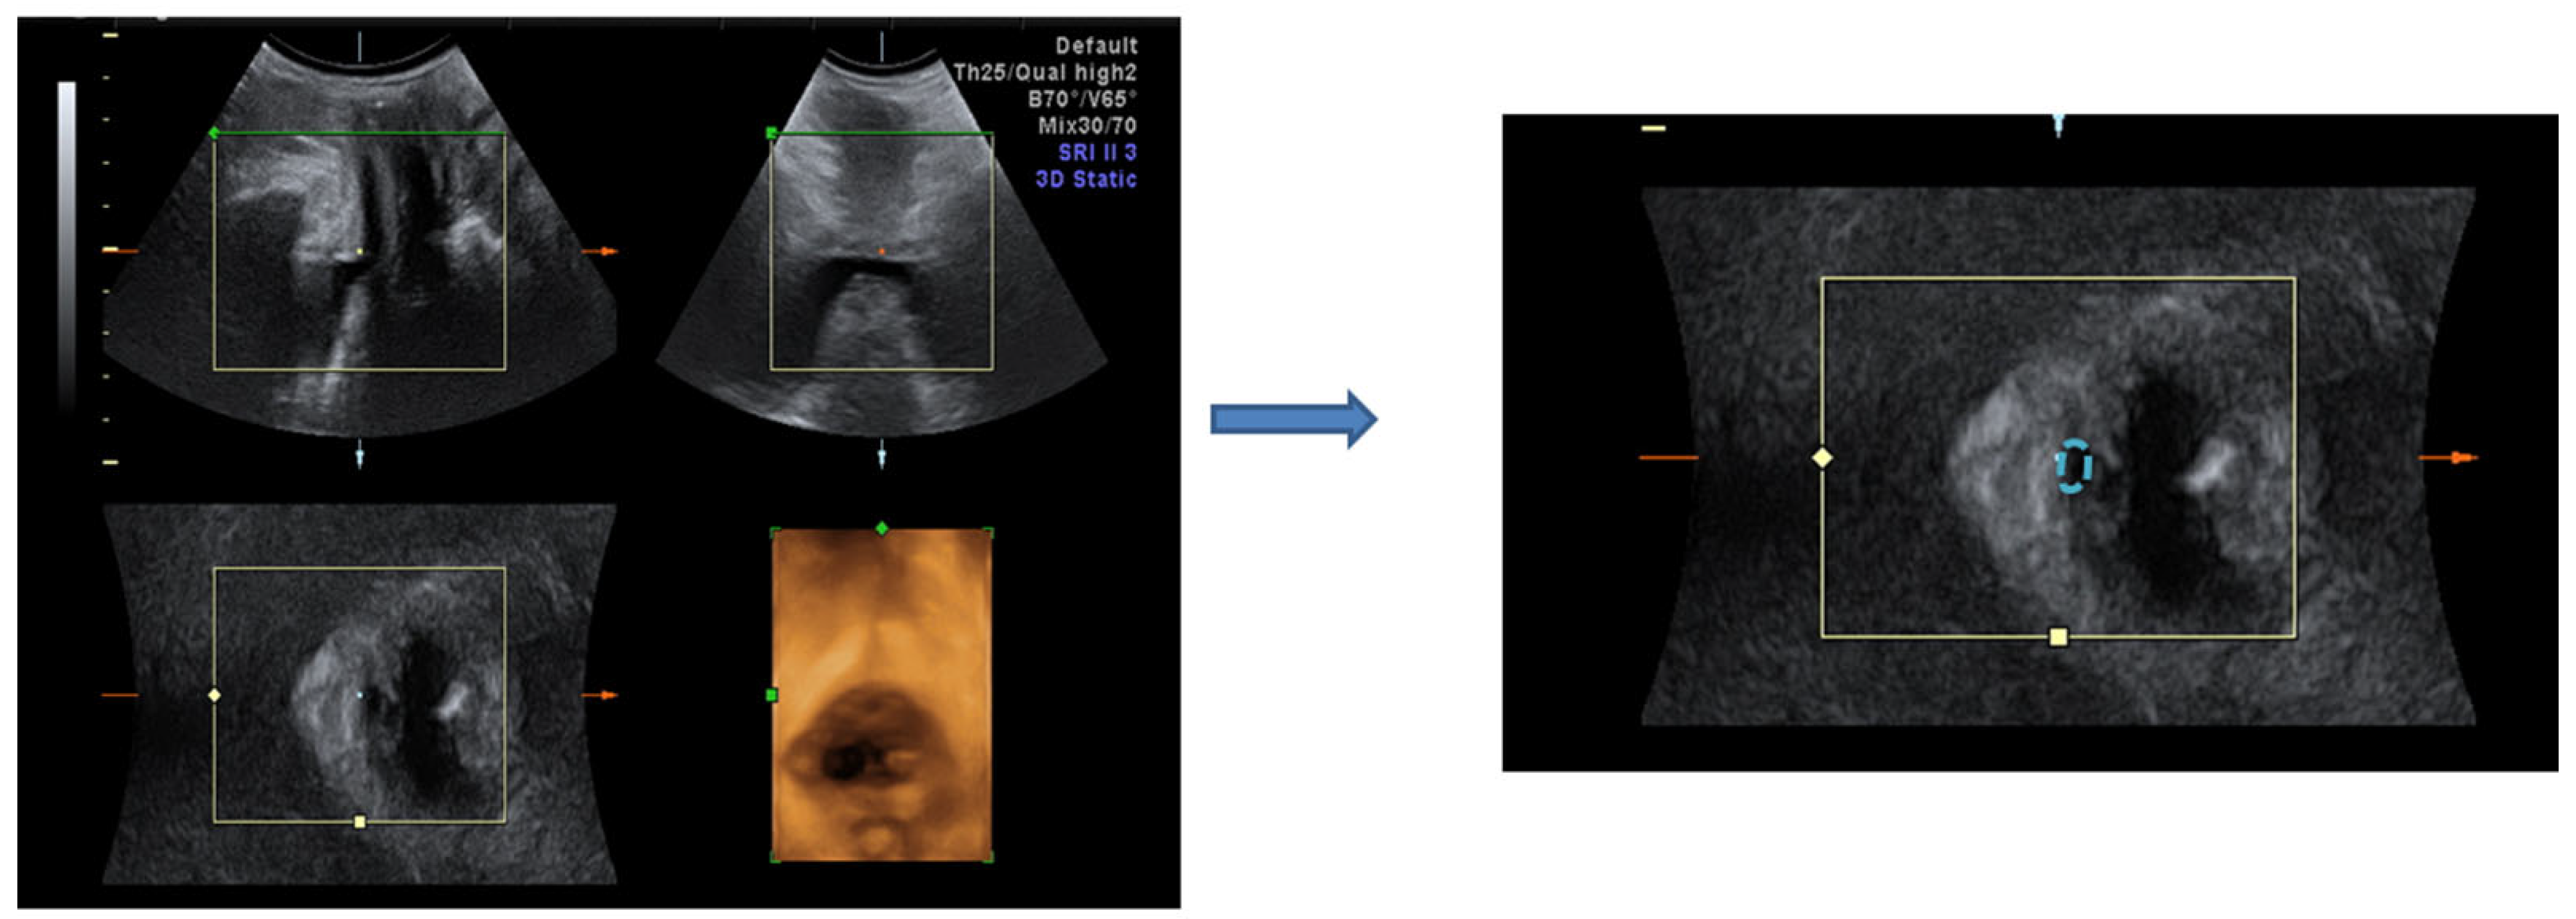

| Bladder neck mobility (mm) | 1.52 ± 0.3 | 1.27 ± 0.3 | 0.043 * | |

| Urethral area (mm2) Resting | proximal | 3.2 ± 1.8 | 2.7 ± 0.6 | 0.122 |

| middle | 2.8 ± 1.1 | 2.2 ± 0.7 | 0.045 * | |

| distal | 2.3 ± 1.0 | 2.5 ± 1.2 | 0.787 | |

| Urethral area (mm2) Straining | proximal | 4.1 ± 1.3 | 4.2 ± 1.1 | 0.574 |

| middle | 3.5 ± 1.2 | 3.2 ± 0.8 | 0.024 * | |

| distal | 2.9 ± 1.0 | 3 ± 1.5 | 0.746 | |